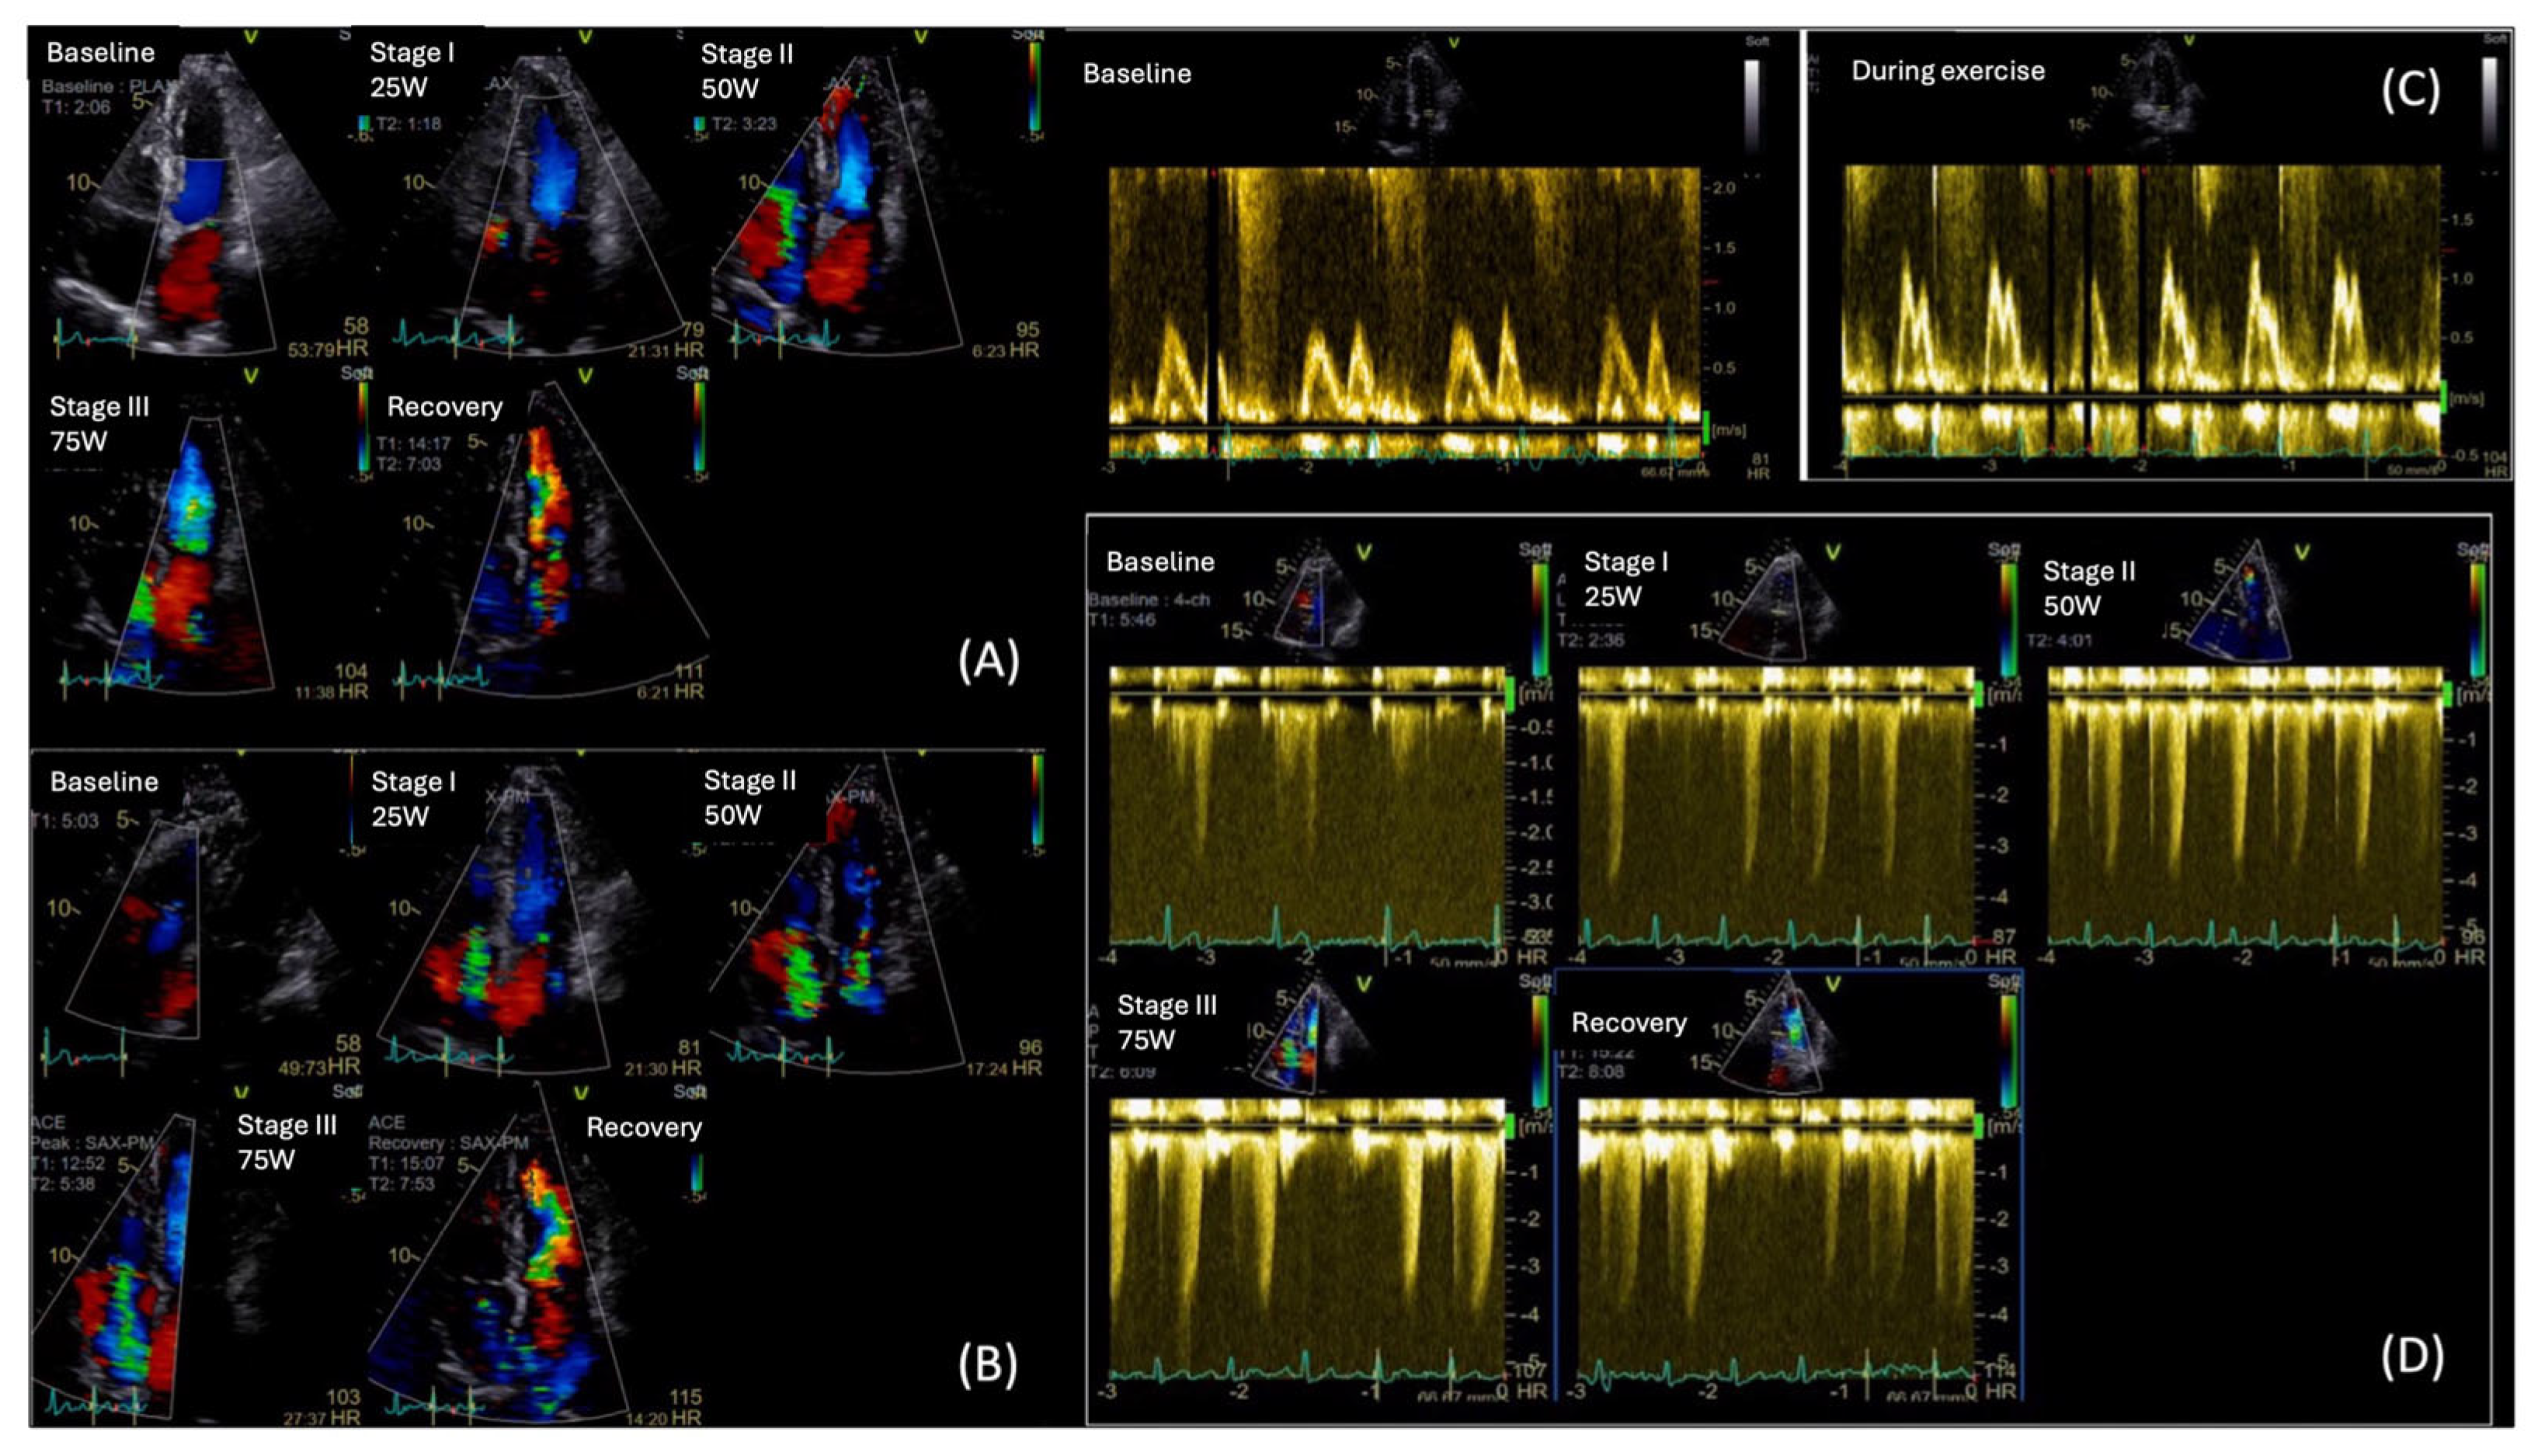

5.1. Exercise Stress Echocardiography

- Gojevic, T.; Van Ryckeghem, L.; Jogani, S.; Frederix, I.; Bakelants, E.; Petit, T.; Stroobants, S.; Dendale, P.; Bito, V.; Herbots, L.; et al. Pulmonary hypertension during exercise underlies unexplained exertional dyspnoea in patients with Type 2 diabetes. Eur. J. Prev. Cardiol. 2023, 30, 37–45. [Google Scholar] [CrossRef] [PubMed]

- Duan, Y.; Ye, L.; Shu, Q.; Huang, Y.; Zhang, H.; Zhang, Q.; Ding, G.; Deng, Y.; Li, C.; Yin, L.; et al. Abnormal left ventricular systolic reserve function detected by treadmill exercise stress echocardiography in asymptomatic type 2 diabetes. Front. Cardiovasc. Med. 2023, 10, 1253440. [Google Scholar] [CrossRef]

| Stress Echocardiography | E/E’ and TRVpeak during DSTE; less evidenced: Coronary flow reserve (CFR), LV contractile reserve, HR Reserve (HRR), mPAP/CO slope | DSTE has been incorporated in HFpEF algorithm; Requires equipment and expertise | Reduced CFR & HRR linked with MACE and mortality even in ischemia-negative stress tests |